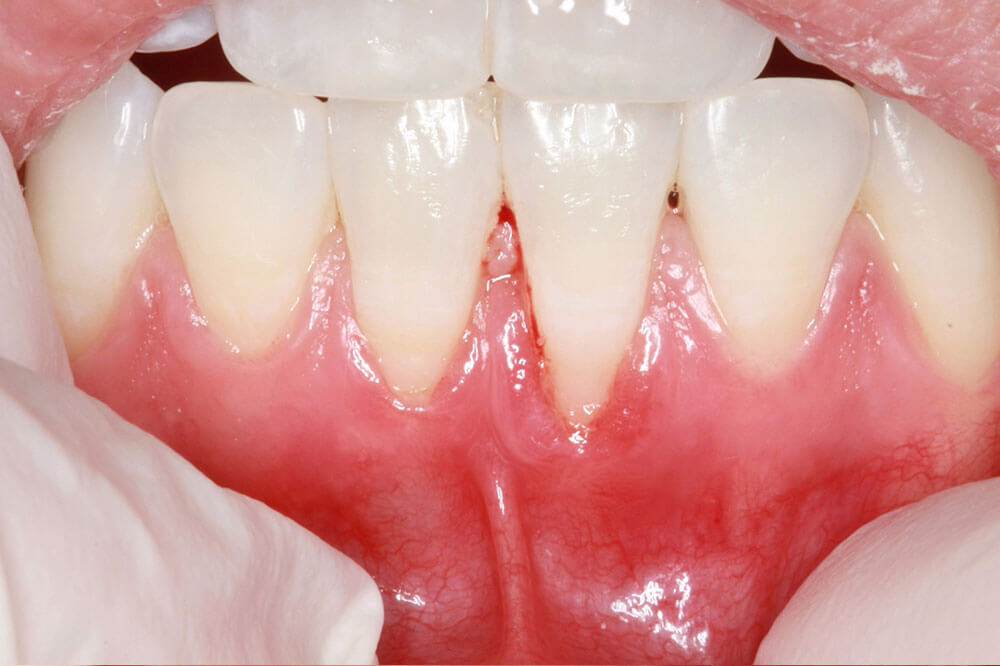

In some cases, a person may simply inherit thin gums that are more susceptible to. Gingival recession, also known as receding gums, is the exposure in the roots of the teeth caused by a loss of gum tissue and/or retraction of the gingival margin from the crown of the teeth. Preventing gum recession is the best approach.

There are few diseases such as gingival recession, periodontal. Gum recession (gingival recession) means the gum tissue surrounding the teeth wearing away or pulling back from the tooth. The most common treatments for gum recession are as follows:

Stopping active gum recession in its tracks takes second place. Brushing harshly can cause receding gum. Gum recession is the process in which the margin of the gum tissue that surrounds the teeth wears away, or pulls back, exposing more of the tooth, or the.